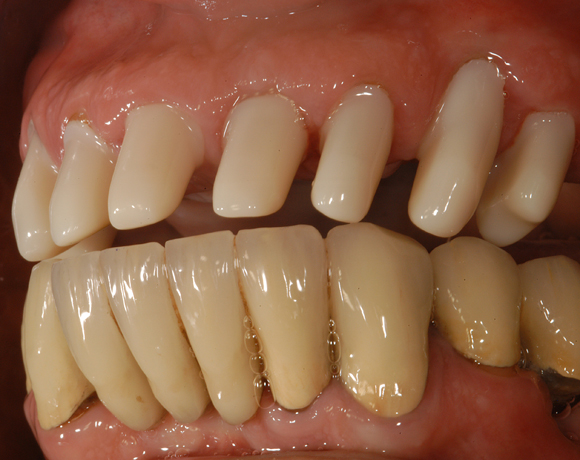

Im vorliegenden Patientenfall musste eine komplette Neukonstruktion der Oberkieferversorgung vorgenommen werden, da auf Grund parodontaler Probleme die Seitenzahnbrücken 15 – 17 und 25 – 27 nicht mehr zu halten waren. Die verbliebenen acht Frontzähne bzw. Prämolaren waren auch parodontal vorgeschädigt und es war ungewiss wie lange sie einzelne noch halten lassen. Um nicht bei jedem Verlust eines der Restzähne eine Neukonstruktion zu brauchen, hat man sich für eine Teleskopprothese entschieden. Für den Patienten war es allerdings nicht vorstellbar goldfarbene Primärteile im Mund zu haben, so wurde der Versuch unternommen diese aus e.max Press und Galvano Sekundärteilen herzustellen.